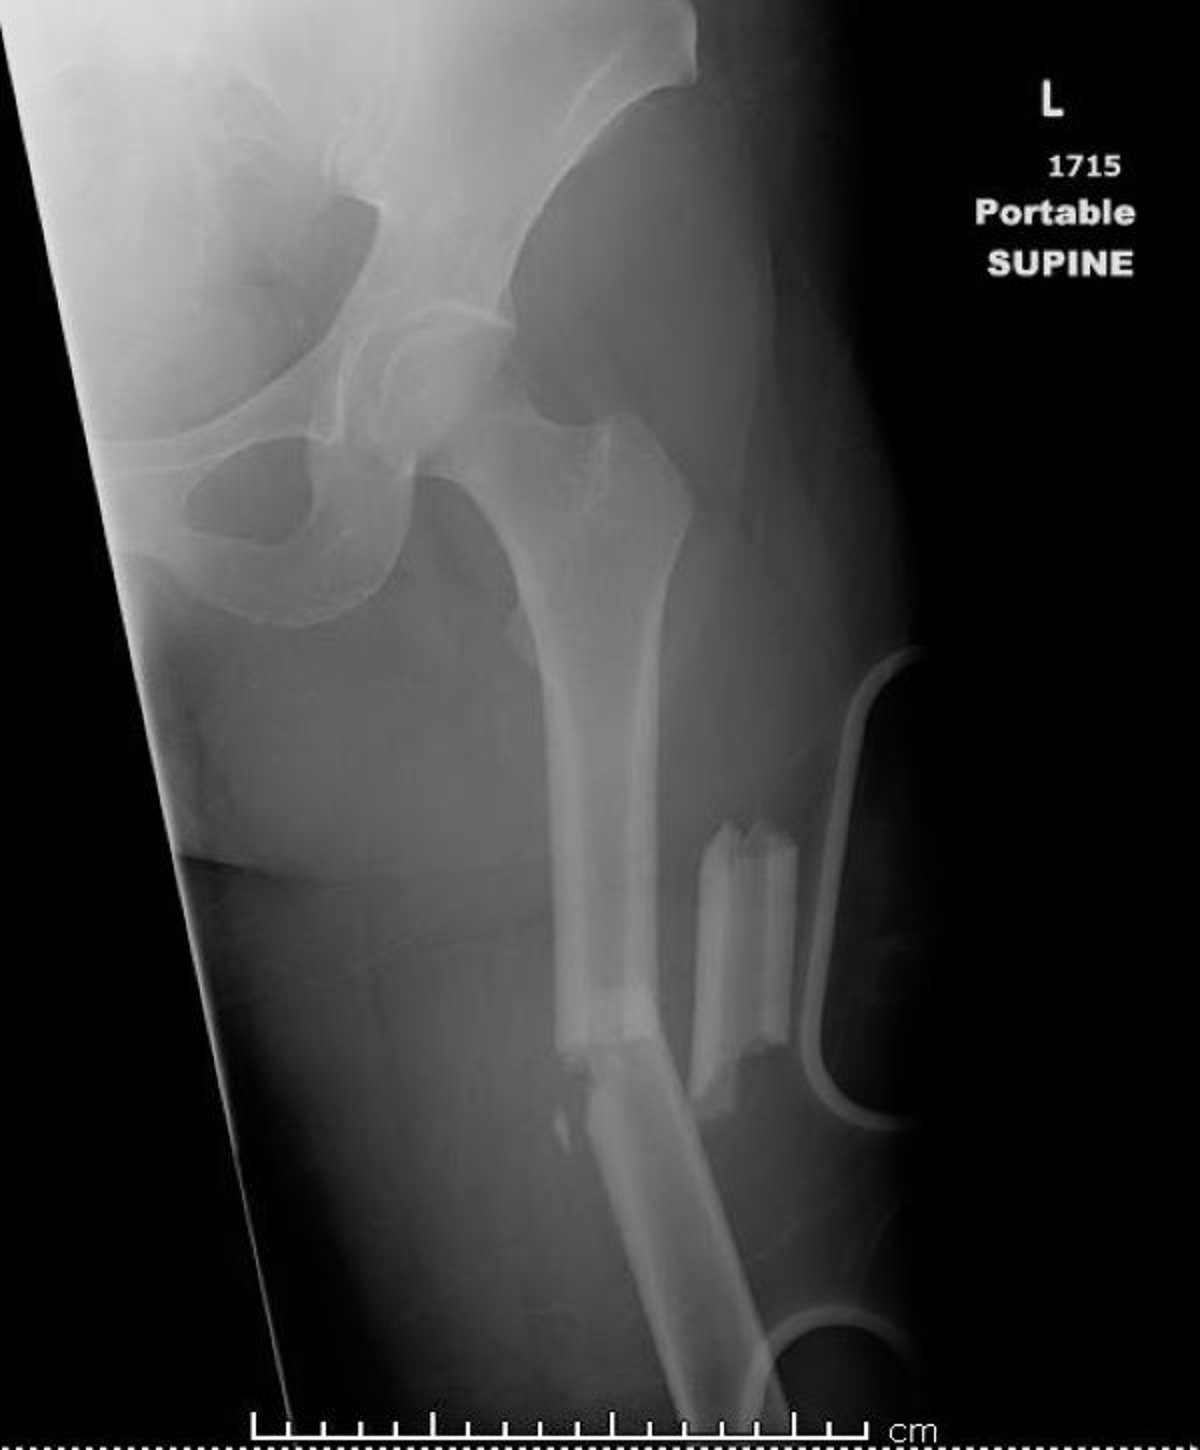

मिडशाफ़्ट जांघ की हड्डी का फ्रैक्चर

यह छवि एक फ़ीमर दिखाती है जो दो से अधिक स्थानों पर टूटी हुई (विखंडित) है।

डैनिएल कैम्पान्ये, MD का छवि सौजन्य।